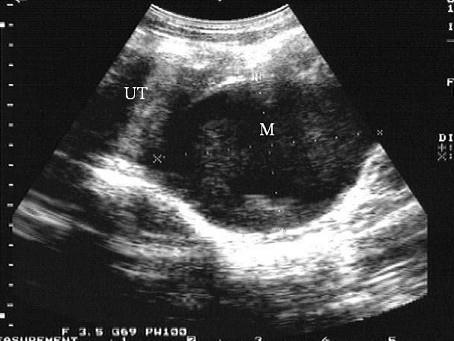

问题 女性,16岁,周期性下腹疼痛伴排尿困难。月经未来潮。超声检查见图,最可能的诊断是 ( )

选项 A、宫颈囊肿 B、子宫肌瘤 C、子宫破裂 D、异位妊娠 E、处女膜闭锁

答案 E